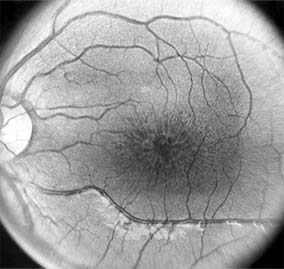

CENTRAL SEROUS CHORIORETINOPATHY

Central serous chorioretinopathy is characterized by serous detachment of the sensory retina as a consequence of focal leakage of fluid from the choriocapillaris through a defect in the retinal pigment epithelium (Figures 10-2 and 10-3). This disease typically affects young to middle-aged men and may be related to life stress events. Most patients present with the sudden onset of blurred vision, micropsia, metamorphopsia, and central scotoma. Visual acuity is often only moderately decreased and may be improved to near-normal with a small hyperopic correction.

Figure 10-2

Figure 10-2: Central serous chorioretinopathy with sensory retinal detachment (arrows) extending into the fovea.

Figure 10-3

Figure 10-3: Fluorescein angiogram of central serous chorioretinopathy shows active disease with both a retinal pigment epithelial detachment (small arrows) and a sensory retinal detachment (large arrows). Two foci of inactive disease (open arrows) are also present.